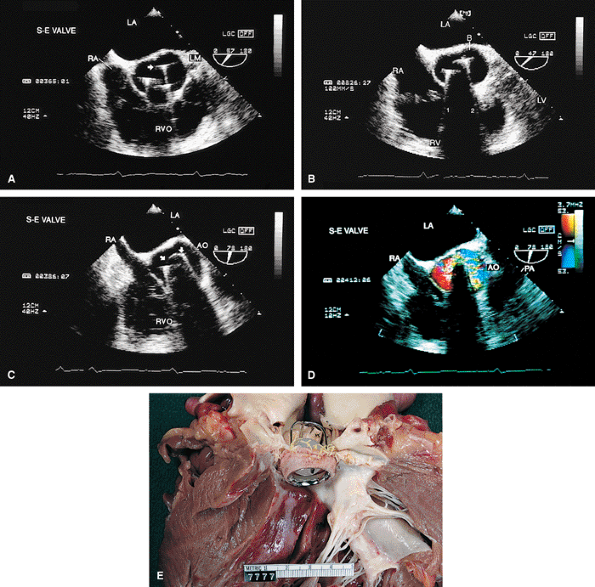

FIGURE 5.2. St. Jude mitral prosthesis: thrombus. A–F. Localized echo densities consistent with thrombus (T) are noted on the St. Jude prosthesis (P) in two different patients (A,B and C–F). In both patients, thrombus prevented the opening of one of the leaflets of the prosthesis. F. Continuous wave Doppler shows a flat velocity profile in early diastole (arrows) and a high peak velocity of 152 cm/sec consistent with obstruction. G and H (one patient) and I (another patient) show two other patients with thrombosed (TH, T) St. Jude mitral prostheses. The echo densities representing thrombus are seen on the atrial side of the prosthesis. Thrombi are less dense than the metallic components of the prosthesis and are different from prosthetic reverberations, which are anteriorly directed, more prominent, and have larger linear echoes. In addition, reverberations are not seen on the atrial aspect of the prosthesis. AO, aorta; LA, left atrium; LV, left ventricle; MP, mitral prosthesis; RA, right atrium; RV, right ventricle; RVO, right ventricular outflow tract. |